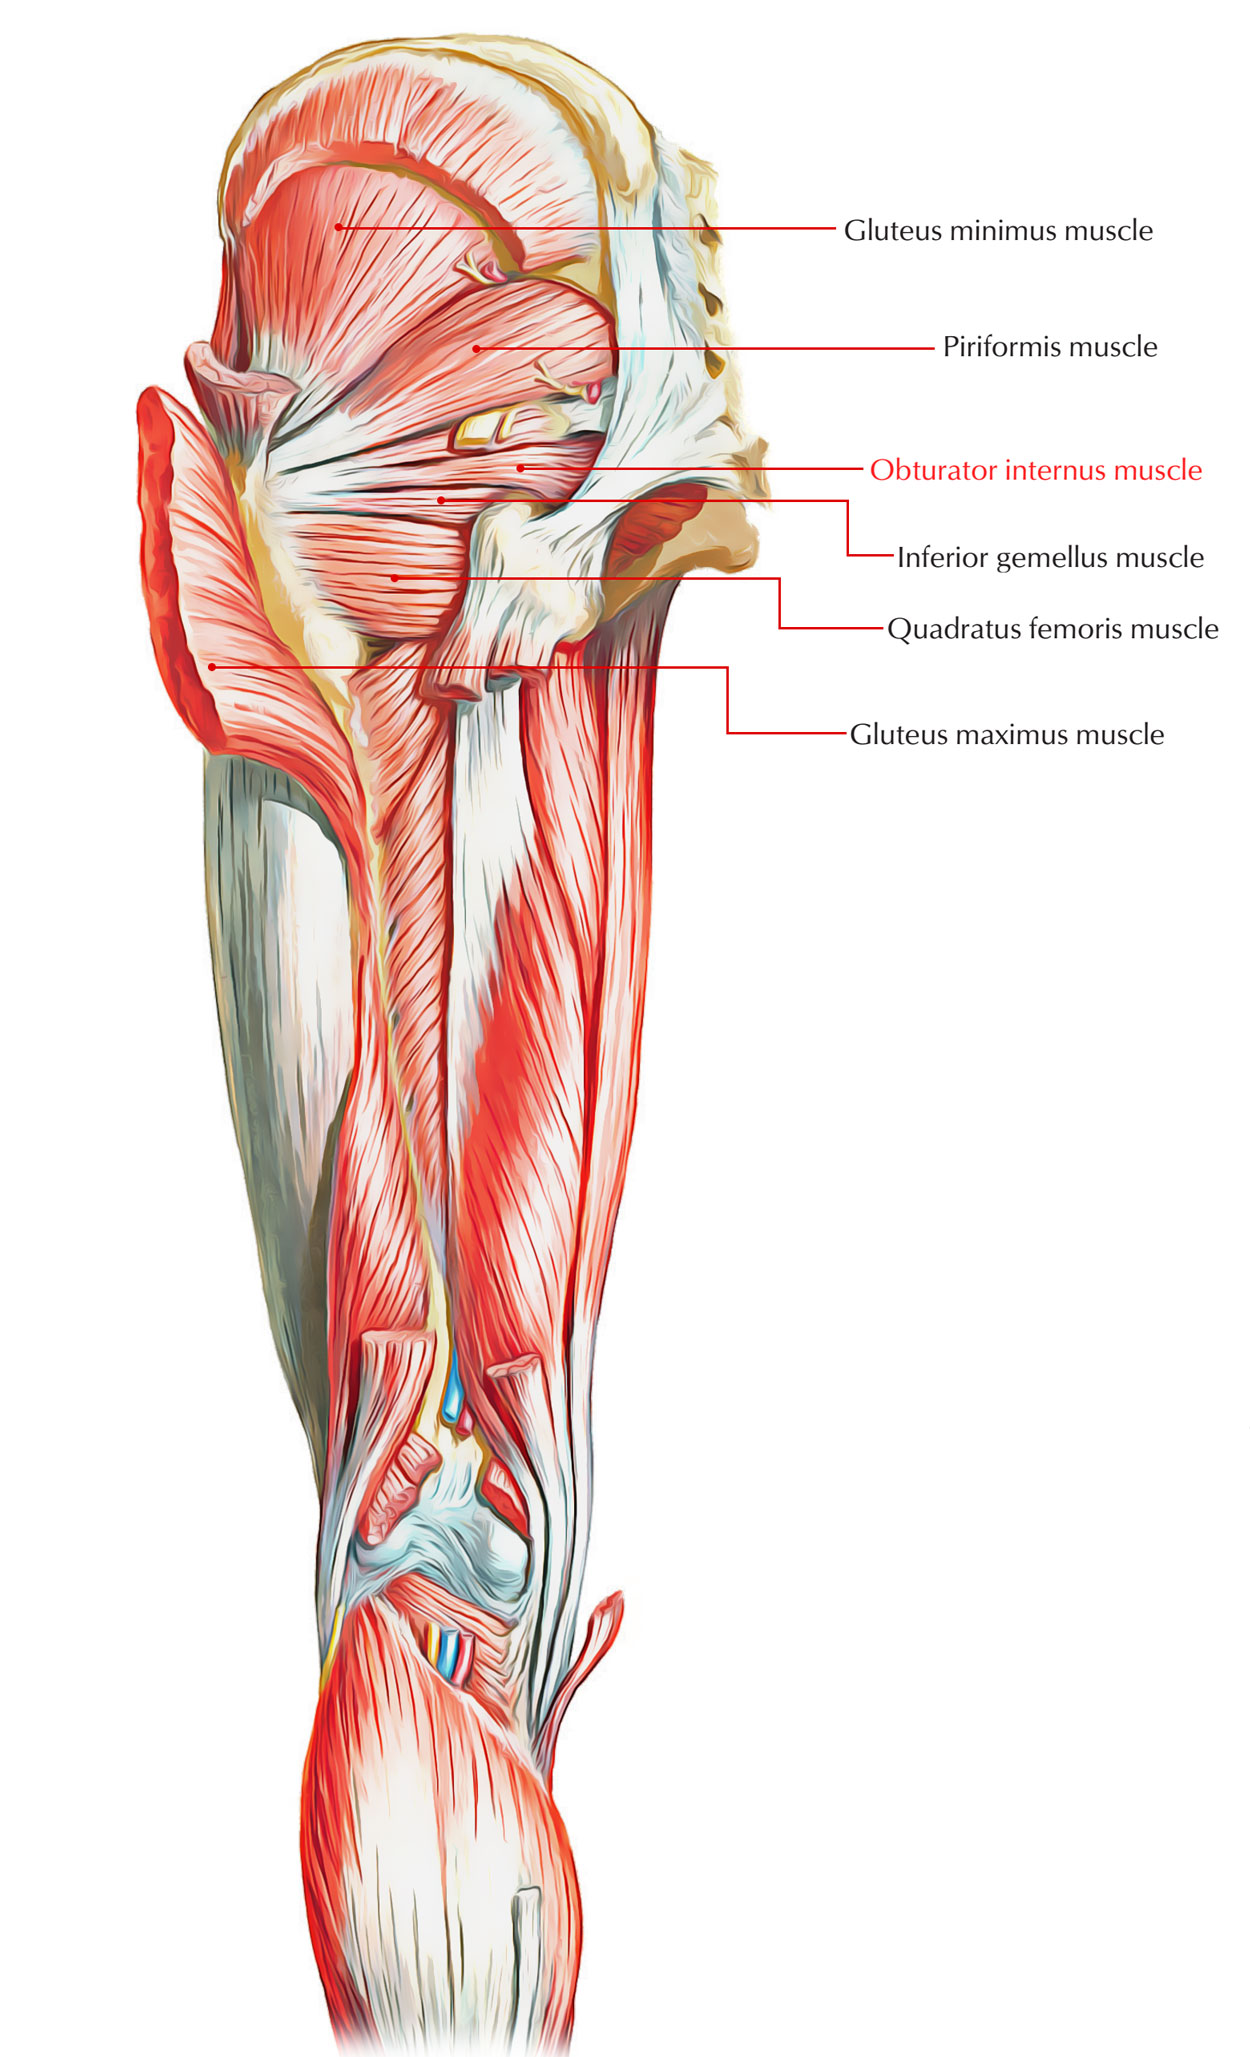

Анатомия мышц: Пириформис